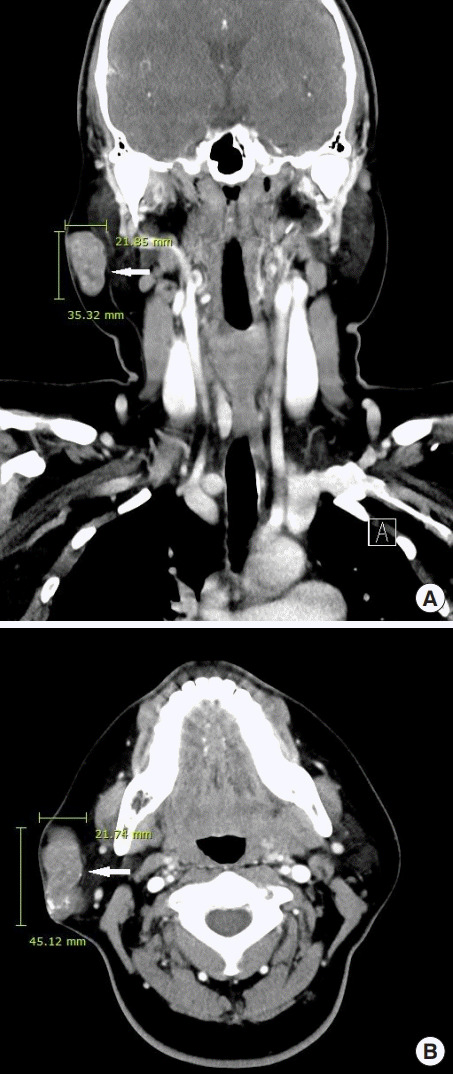

诊断时为35岁的张雨绮(女,化名)右侧腮腺区有肿块,就诊于佳学基因检测合作医院的整形外科。 肿块直径约 1 cm,张雨绮因无临床症状而拒绝手术切除。 然而,在怀孕的中晚期,肿块的大小增加到 5 厘米(图 1),并且变得疼痛。 分娩后肿块停止生长。 触诊肿块时,患者报告疼痛从腮腺区放射至耳后区。 病灶摸起来温暖、坚硬、淡蓝色和分叶状。 由于临床症状加重,患者同意接受手术切除肿块。

毛母质瘤是一种良性皮肤肿瘤,起源于分化为毛母质细胞的表皮原始基底细胞。 大多数毛母质瘤的直径约为 1 厘米,而直径为 5 厘米或以上的则被归类为巨大毛母质瘤。 头颈部毛母质瘤的鉴别诊断包括皮脂腺囊肿、骨化性血肿、鳃残余、耳前窦、淋巴结肿大、巨细胞瘤、软骨瘤、皮样囊肿、退化性纤维黄瘤、异物反应、皮肤骨瘤。 正确诊断毛母质瘤需要放射影像学和组织病理学检查。 其组织病理学特征包括外围的细胞簇(包括有核基底样细胞)和中心的无核影细胞(也称为“鬼细胞”)呈圆形排列。 巨大的毛母质瘤通常与外伤有关,并且有时会在外伤事件后观察到溃疡或坏死组织物质的局灶性经表皮消除。